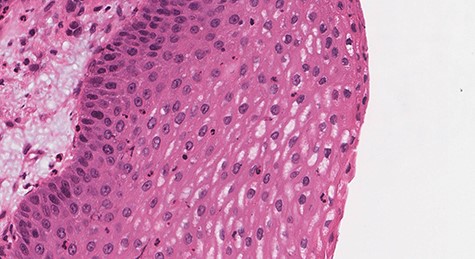

Histologic sections show an endophytic (inverted) pattern that grows downward into the underlying stroma (Fig. 4). The epithelium consists of hyperplastic squamous epithelium (Fig. 5) and ciliated columnar cells admixed with scattered mucocyets (goblet cells) (Fig. 6). The cells have a bland appearance and uniform small nuclei. No cytologic atypia, increased mitotic activity or necrosis seen. Mixed inflammatory cells are dispersed within the epithelium and stroma.

![Section of IP (hematoxylin and eosin [H&E] stain; ×29).](https://oupdevcdn.silverchair-staging.com/oup/backfile/Content_public/Journal/jscr/2020/8/10.1093_jscr_rjaa180/1/m_rjaa180f4.jpeg?Expires=1768215475&Signature=QmVacpIIfI1DV9jAlGaE1Tm9jahPyGfO1Ak4PqzqFm2a72hfuv0vgQ9pinaI8DYl2nWFcBqNe35AWimZPypVp-taU3Z2vcuv6VK64FS4-67clY-oaa0p0BA3yQXAlDlQwBc6maiYx3y0oMbuoPFfX2WhQvgd58Ma~nHTHei5OEJDWJGI5SIe5yU5GwcsQsZ30wfsHXn4kcr2KQmUzWBsXY6yMneptM5Syt3qSk3y0HFQkmAuFRIVFTW2KKYwIP092WxMOuOhrlZ7~hUcTsYxm4baxo2UU89-0bhJCDpNzSTyte4N71f1K2VZx9hCPsiL6tyTJZnAahoXRr9BqubBxQ__&Key-Pair-Id=APKAIYYTVHKX7JZB5EAA)